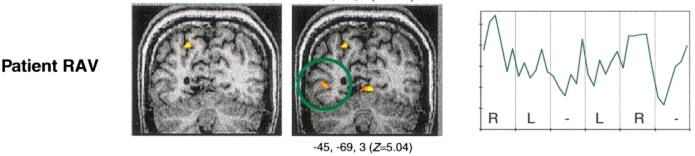

RECONNAISSANCE VISUELLE DES MOTS ET PLASTICITE CEREBRALE

Ressources reconnaissance visuelle des mots